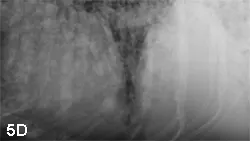

With increased opacity, many diseases will present with a mixed pulmonary pattern, so the dominant pattern should be identified to formulate an appropriate differential list (Figure 5). More important, the anatomic distribution will drive the prioritization process for differentials. For example, cranioventral typically equates with infectious disease (bacterial pneumonia), whereas caudodorsal typically equates with edema (cardiogenic or noncardiogenic).

Lateral radiographs from various dogs with increased lung opacity; ventral alveolar pulmonary pattern (A), generalized bronchial pulmonary pattern (B), vascular pulmonary pattern in a dog with a left-to-right shunting patent ductus arteriosus (C), structured interstitial pulmonary pattern in a dog with pulmonary nodules secondary to renal carcinoma metastatic disease (D), and an unstructured interstitial pulmonary pattern (E)